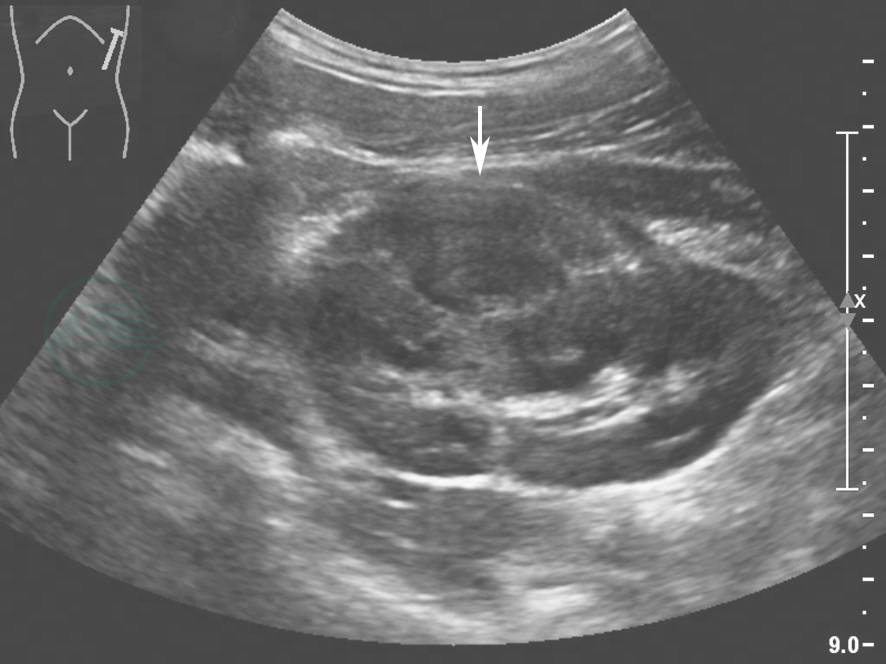

Ⅰ~Ⅲ级肾外伤的超声声像图表现与损伤部位及出血时间有关,位于肾实质的病灶多呈低回声,而位于肾包膜下或肾周的血肿回声类型多变,其中急性出血呈无回声或弱回声,30min后出血会产生自凝,回声也逐渐增强呈高回声,4~5d后,因凝血块液化,超声表现为低回声甚至无回声(图1),随后被身体逐渐吸收,2~3个月后未被吸收的血肿可形成钙化,表现为强回声。Ⅰ~Ⅲ级肾外伤的肾裂伤处及肾包膜下血肿、肾周血肿、尿外渗内均无彩色血流信号,但裂伤以外的血流信号正常存在。

图1肾周血肿超声图像